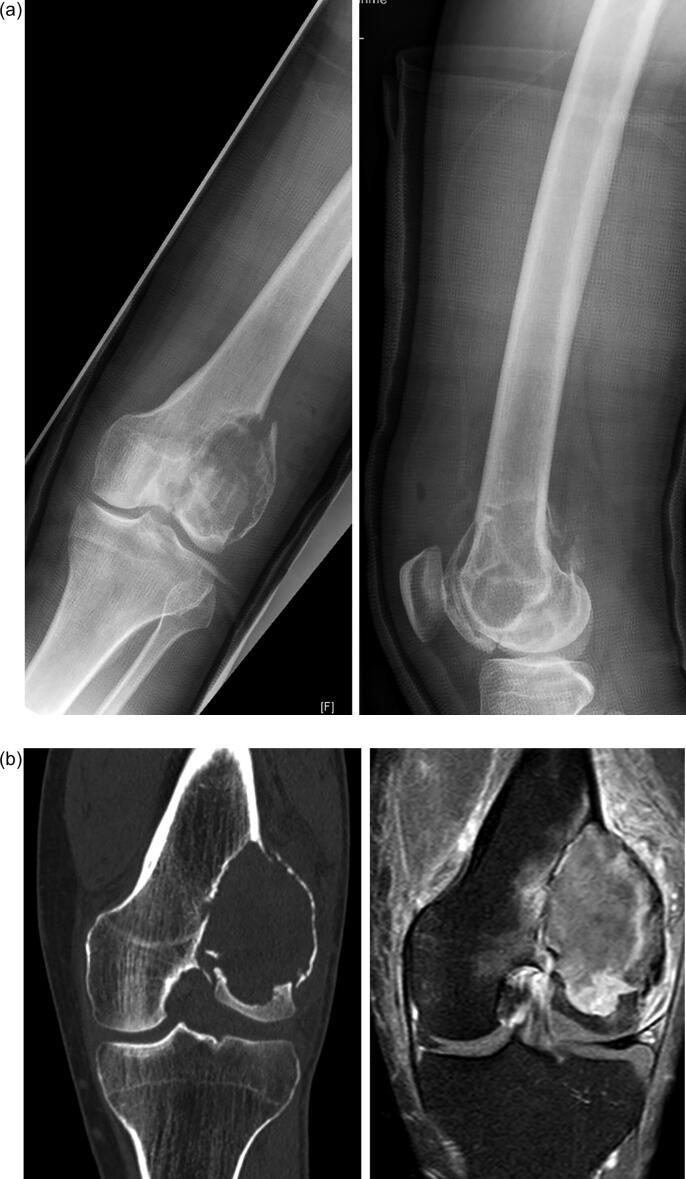

Giant cell tumor of bone (GCTB) is a locally aggressive bone tumor that represents about 4-5% of all primary bone tumors. It is characterized by aggressive growth, possible recurrence after surgical treatment and, in rare cases, metastasis. Surgical management is the primary treatment and may include intralesional curettage with adjuvants or, in rare cases, wide resection. In recent years the monoclonal antibody denosumab has been introduced as a potential (neo-)adjuvant systemic treatment option for patients with borderline resectable or unresectable lesions. Currently several studies reported that the use of denosumab prior to curettage possibly increase the risk of local recurrence.

https://cdn.ncbi.nlm.nih.gov/pmc/blobs/e9da/8881473/3c8a32a2e9d9/gr1.jpg